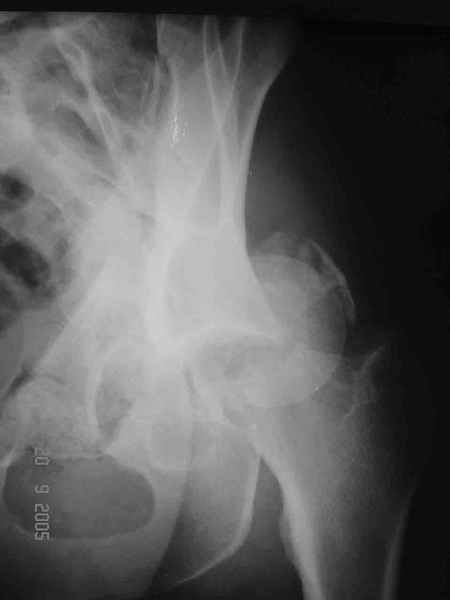

Привет! Вот недавно прооперировали похожий на ваш случай - впадина + шейка (правда у нас впадина поперечный+задний край). После травмы прошло 4 недели. мужчине 46 лет. С такой комбинацией все показания к первичному протезированию. Морально и технически мы к этому уже созрели.Но больной не собрал денег на протез. Выполнили остеосинтез впадины и шейки, прекрасно понимая, что головка вскоре рассосется, мы хотя бы надемся что к этому времени таз срастется, как говорится создали все условия для дальнейшего протезирования (может, и протез в последующем подешевле будет, в смысле, без укрепляющего кольца?). Привет Рункову!